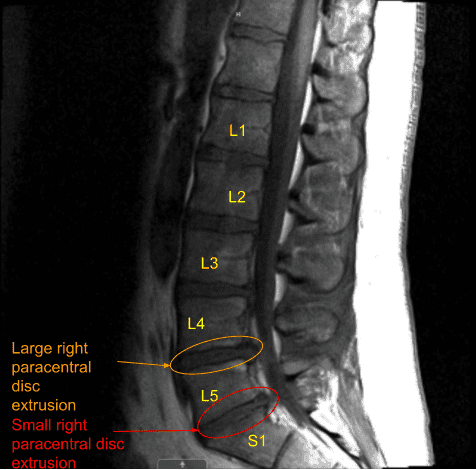

The patient had good relief after the surgery which was followed by recurrence of the pain in two weeks. This was associated with tingling and numbness along with foot drop on the right side. A repeat MRI was done which showed a re-herniation of disc on the right L4-L5.

MRI and CT of Lumbar spine were done which showed degenerative disc disease L4-5 and L5-S1 with re-herniation at L4-5.